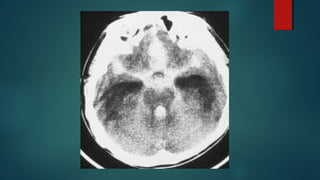

Este documento es el programa para un taller de imágenes del curso de emergencia 2015 impartido por el Dr. Víctor Delgado. El taller se centra en el uso de imágenes médicas para el diagnóstico y tratamiento de pacientes en coma traumático según la base de datos de Marshall. El Dr. Delgado es el único instructor repetido a lo largo del documento.